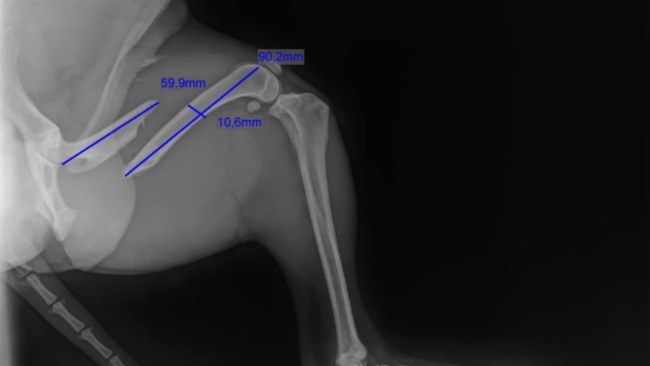

Maksiu ma złamane tylną kość udową i bez operacji nie będzie mógł normalnie chodzić! Zabieg musi odbyć się PILNIE – już 1 kwietnia o 8:00 w przychodni SULXE w Sulejowie. Koszt operacji i leczenia to 2 000 zł, a my nie jesteśmy w stanie sami pokryć tej kwoty.